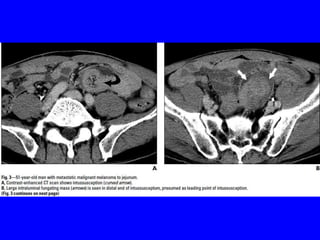

• The SI involvement with metastatic tumors is more common in

melanoma than upper or lower GIT due to its rich blood supply&

appear as intraluminal masses or serosal implants, usually

diagnosed on imaging studies.